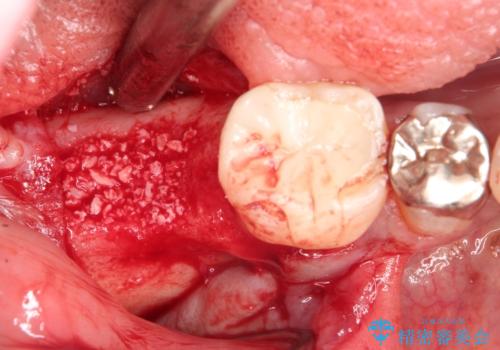

抜歯後十分な骨の回復が認められず、単独の骨増生を行った後にインプラントを埋入しました。

インプラント埋入時に骨が足りない場合にはインプラント埋入前に骨増生を行います。また、インプラント周囲の角化歯肉が不足した場合は角化歯肉の移植も行うことがあります。

どちらの治療もインプラントの長期予後を高めるために必要な治療です。